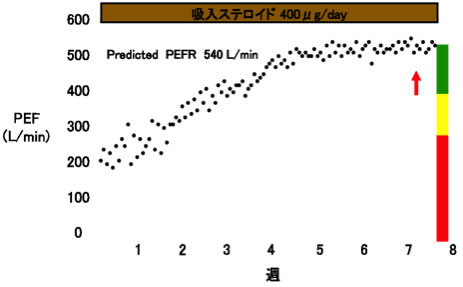

最新の喘息ガイドラインに準じて、「吸入ステロイド(ICS)」と「長時間作用性気管支拡張薬(LABA、LAMA)」などの吸入薬を中心とした標準的な治療法を基本治療として、「抗ロイコトリエン受容体拮抗薬」や「テオフィリン製剤」などの内服薬を適宜追加したりすることで、症状が劇的に改善します。環境アレルゲンの回避や適切な吸入指導も繰り返し行います。喘息の管理は、ピークフローメーターという簡易的な器具を使用して行います。これを用いて患者さん自身で呼吸機能の変化を日誌に記録し、治療の効果や悪化の前兆などを管理します。(図5)。しかし高用量ICSと気管支拡張薬を含む治療を行っても改善しない重症難治性の喘息が5-10%程存在します。これらの重症例では個別化医療の考え方に基づき、アトピー要因のある方に効果が期待される生物学的製剤による治療も積極的に行っております。

図5. 喘息治療におけるピークフロー(PEF)の推移